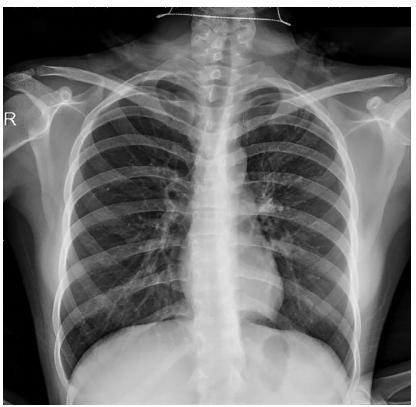

图1 PTB病例值得注意的是,支气管内膜结核(EBTB)属于特殊的PTB,且10%-20%的EBTB者胸部X线无明显异常(见图2)[9],容易出现结核病漏诊。

图2 胸部X线正常的EBTB病例有趣的是,EBTB患者常伴有慢性咳嗽、气促等症状,与哮喘临床表现颇为相似。PTB很少合并哮喘发病,因结核感染可诱导Th1免疫反应,且抑制了以Th2反应为特征的哮喘相关炎症过程[10]。因此,对于以慢性咳嗽、气促为主诉的患者,辨别结核病和哮喘的诊断至关重要。若慢性咳嗽、气促者按照CVA治疗后效果不佳,需怀疑EBTB可能。已知胸部X线对分辨EBTB与哮喘的应用价值不高,可执行支气管舒张(或激发试验)、气管镜检查(含镜下刷检、送检肺泡灌洗液培养等)用于两者的鉴别。